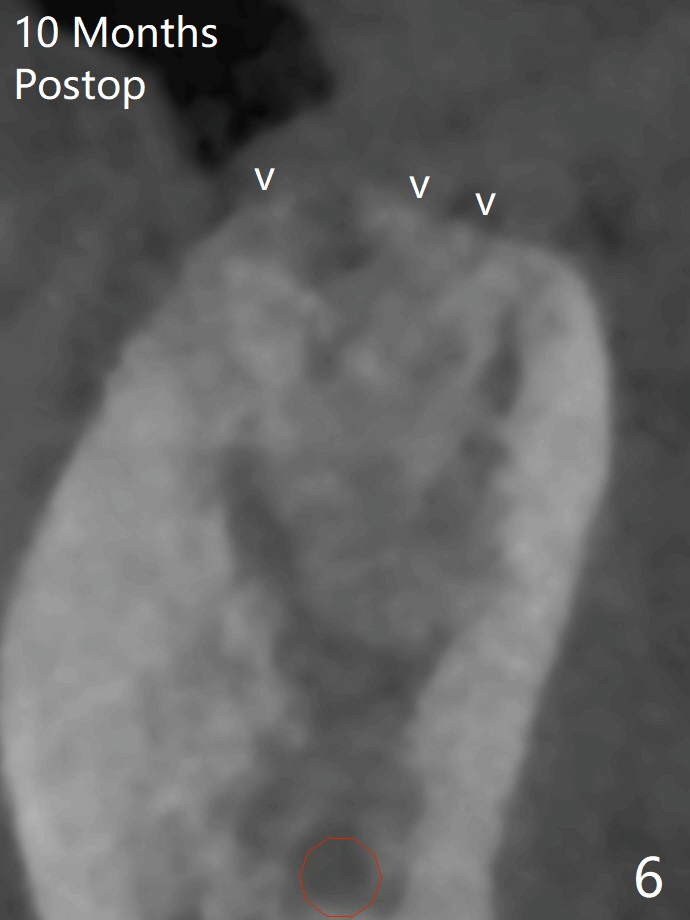

CBCT shows thin cortical bone formation mesiodistally 6.5 months post socket preservation with allograft with PRF at #31 (Fig.3 ^, as compared to Fig.1). The socket appears to be closing buccolingually 10 months postop (Fig.6 arrowheads, as compared to Fig.4). Bone density increases from 1100 units to 1,200-1,400 units 6.5 to 10 months. With underprep (4 mm), a 5x10 mm implant is placed with ~ 50 Ncm with guide (Fig.7). Following a 5.5 mm profile drill, a 5.5x3 mm healing abutment is placed (Fig.8); the implant plateau appears to be supported by the graft bone (*). The implant remains subcrestal 4 months postop (Fig.9).